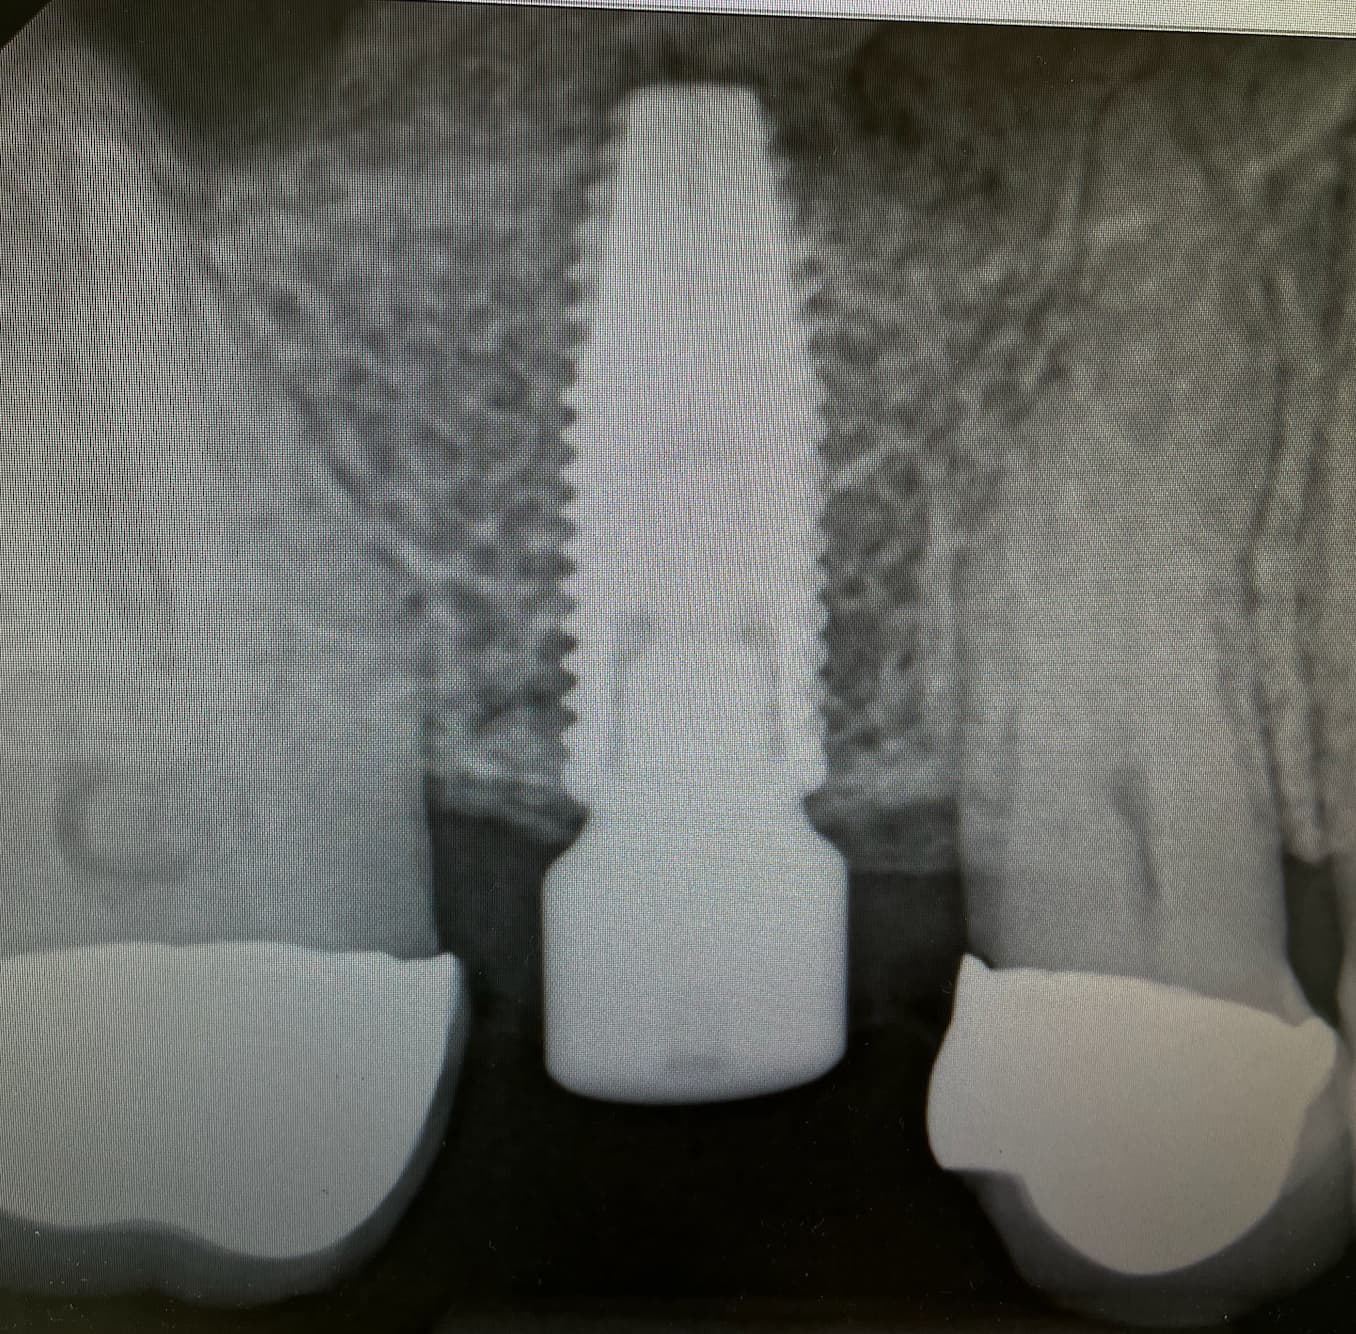

Un implant dentaire est une racine artificielle en titane insérée dans l'os de la mâchoire pour remplacer une dent manquante ou extraite. Le titane est un alliage biocompatible qui permet à l’os de se fusionner avec la surface implantaire, processus qu’on appelle l’ostéointégration. Un implant est conçu pour servir de support solide et durable à une prothèse dentaire telle qu'une couronne, un pont ou une prothèse dentaire complète.

Le processus commence par une consultation avec un de nos chirurgiens. Il évaluera l'état de votre santé bucco-dentaire, prendra des radiographies et discutera des options de traitements.